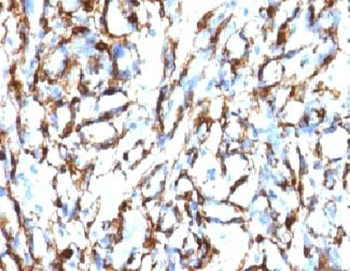

IHC: Formalin-fixed, paraffin-embedded Leiomyosarcoma stained with Smooth Muscle Actin antibody (clone SPM332).